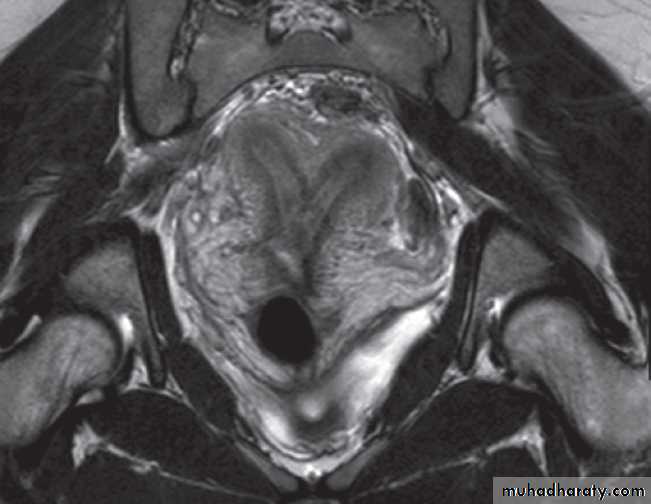

At CT fibroids are usually the same density as the adjacent myometrium. MRI can readily identify fibroids as they typically have a different signal characteristic from the normal uterus .

Adenomyosis

Adenomyosis is a benign condition in which there is endometrial tissue within the myometrium. This results in smooth muscle hypertrophy. Patients may present with dysmenorrhoea and abnormal uterine bleeding. The uterus is typically enlarged.On ultrasound, there is increased heterogeneity of the myometrium.

On MRI, there is focal or diffuse thickening of the junctional zone and, in some cases, multiple bright projections are seen extending from the endometrium into the myometrium .